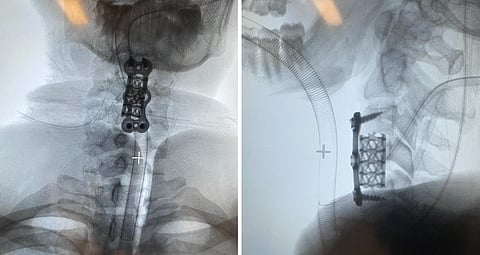

باشر الفريق الطبي على الفور إجراء عملية جراحية لإزالة الفقرة العنقية الرابعة وتحرير الحبل الشوكي، مع تركيب قفص كربوني بديل للفقرة المزالة وتثبيته بشرائح ومسامير. وبعد إزالة الفقرة العنقية الرابعة وتركيب القفص الكربوني، تولى الأطباء رفع الكسر المنخسف بعظم الجمجمة وتفريغ النزيف فوق الأم الجافية، ثم اختتموا الإجراءات الجراحية بتثبيت كسر الفخذ بالشرائح والمسامير.

وقد استغرقت العمليات الثلاث نحو ثماني ساعات متواصلة، نُقل بعدها المريض إلى العناية المركزة لمدة 24 ساعة تحت الملاحظة الدقيقة، ثم جرى نقله إلى القسم وهو بكامل وعيه، مع تحسن ملحوظ في حركة الأطراف العلوية ليصل مقياس الحركة إلى 4+/5 بعد الجراحة مباشرة.